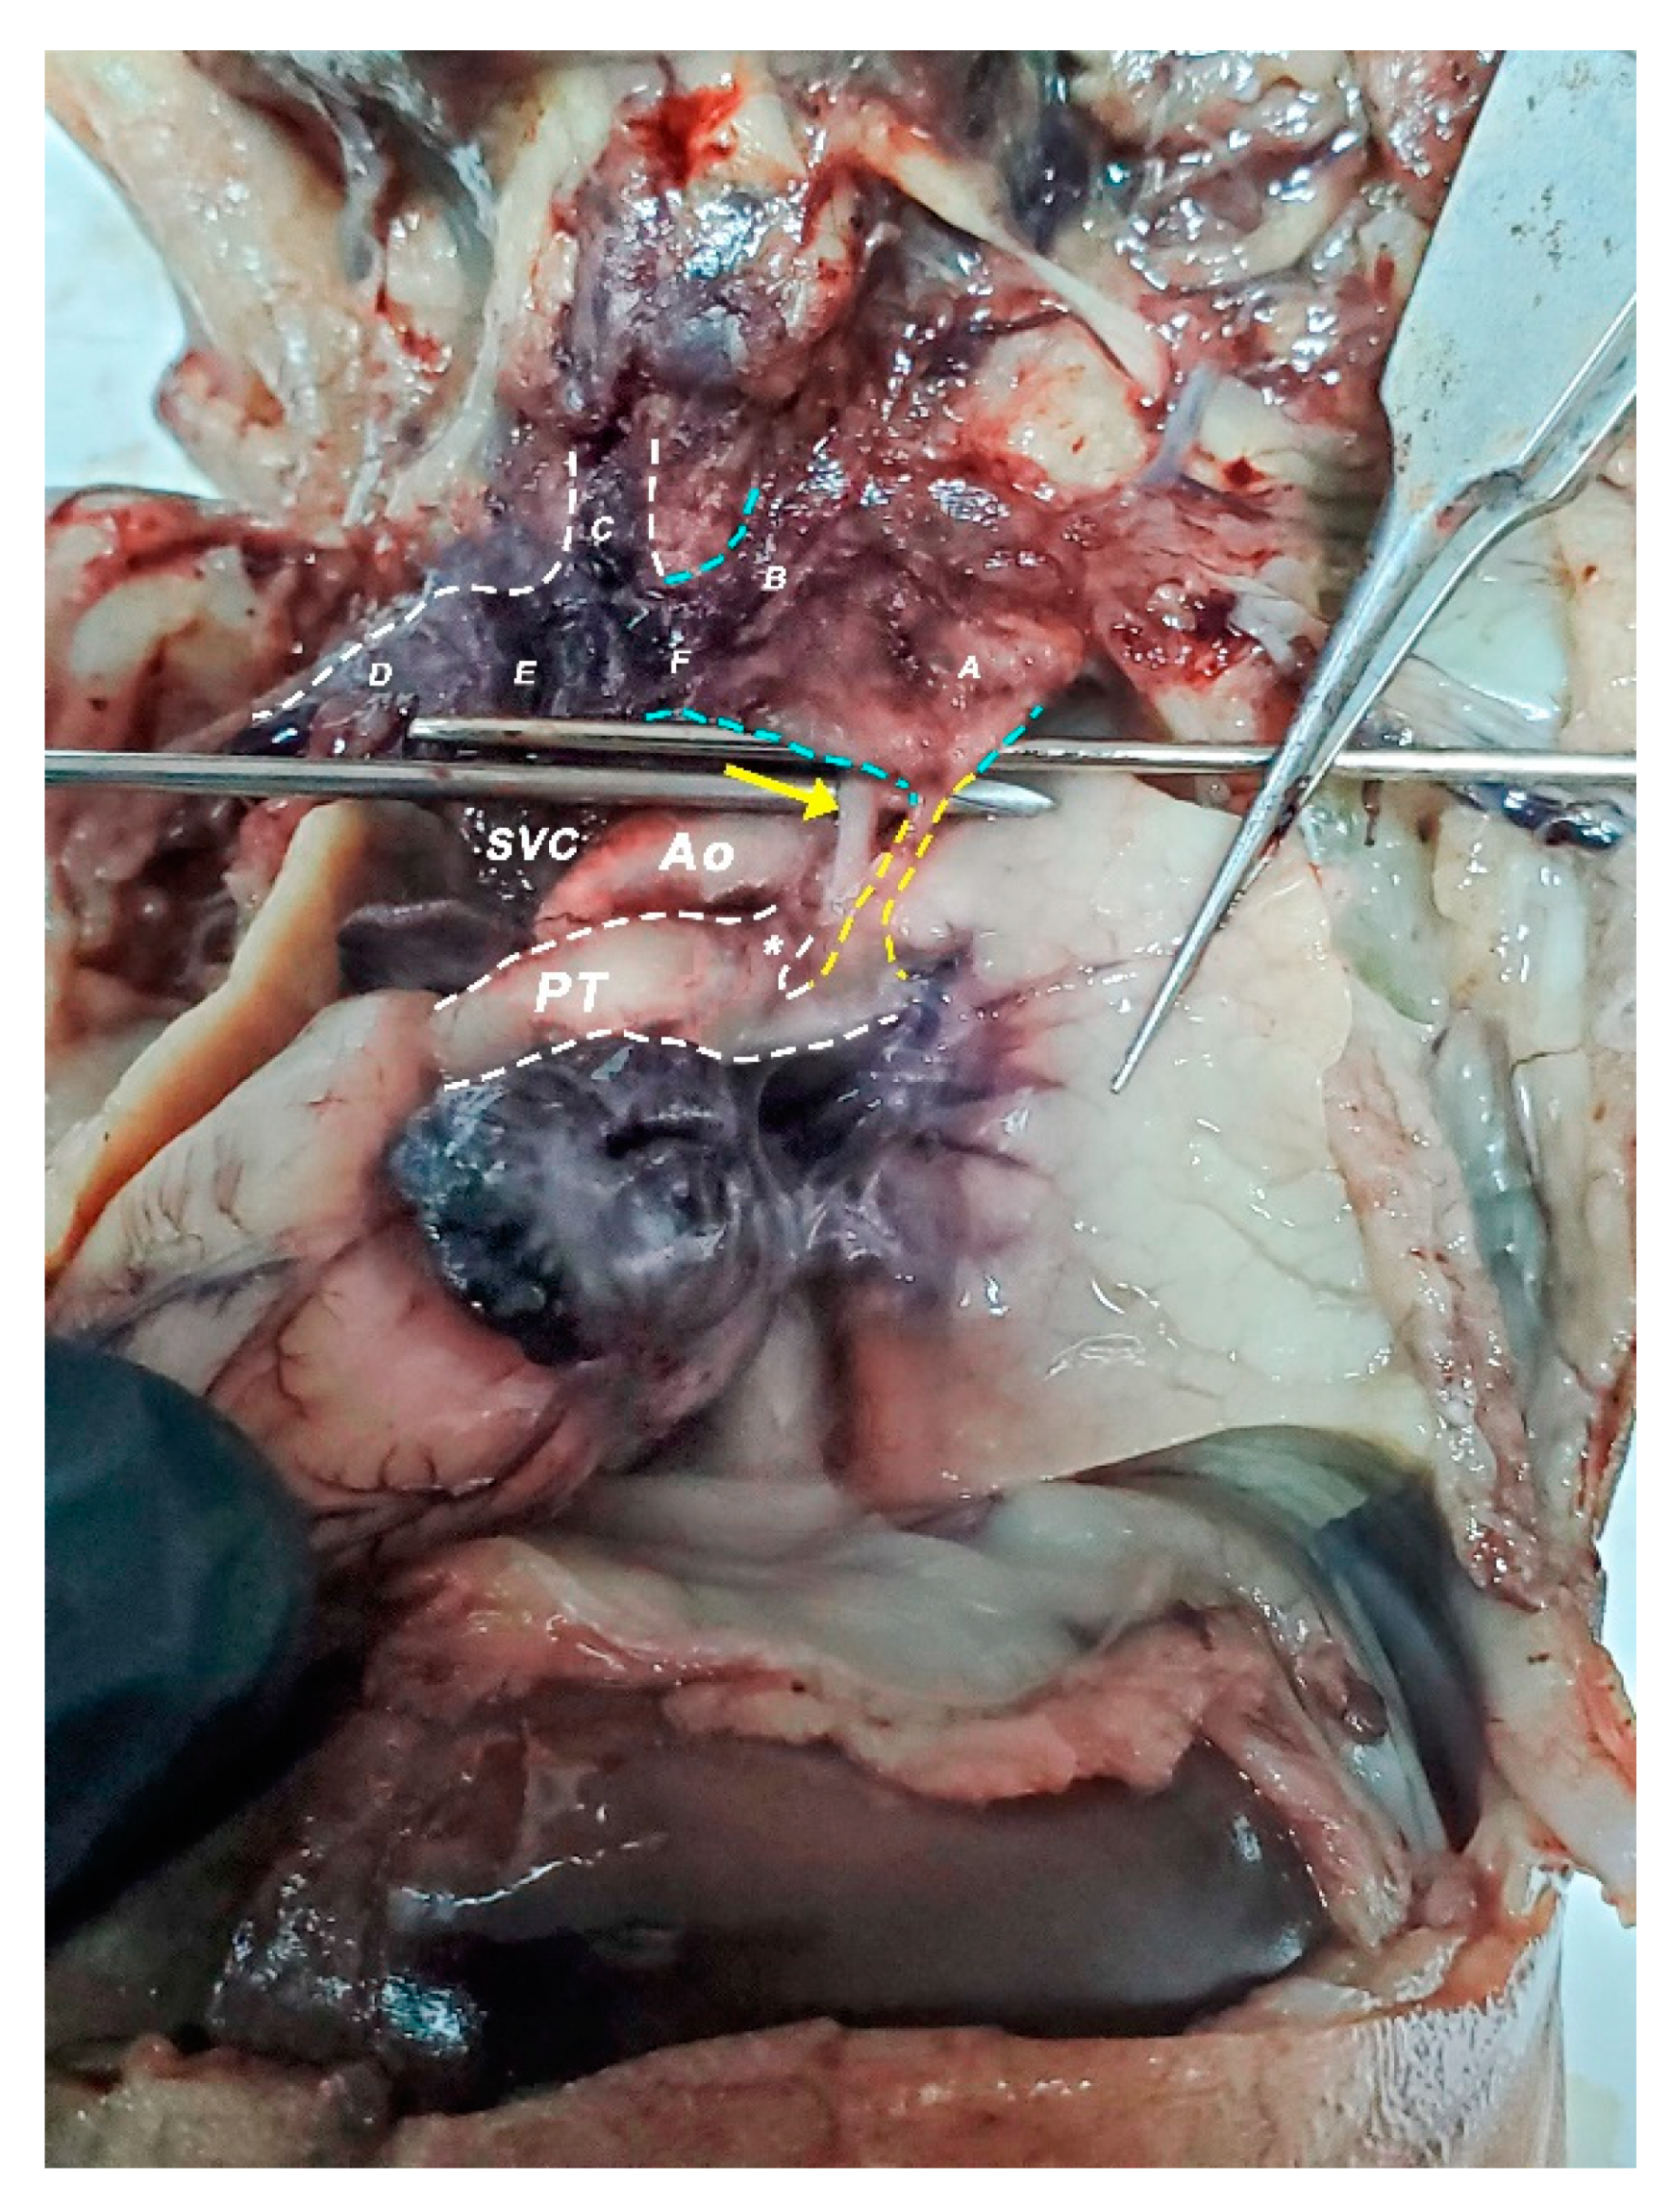

2.2. Dissection